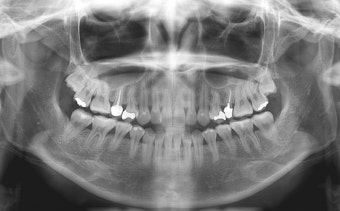

- 임플란트·틀니는 3~6개월마다 정기 검진 필수. 초기 3개월은 적응 기간.

- 자연 치아 vs 임플란트: 자연 치아는 완충 역할을 하는 치주 인대가 있으나, 임플란트는 없어 합병증 발생 위험↑.

- 합병증(나사 풀림, 파절 등)은 초기 자각 어려움 → 정기 검진 필수.

- 조기 검진은 작은 문제도 빠르게 발견 → 큰 문제 예방 가능.

- 최소 6개월마다 구강 검진 권장 → 큰 증상 없어도 예방 차원 중요.